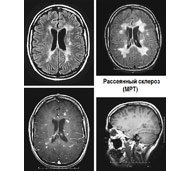

Магнитно-резонансная томография (МРТ)

Это исследование использует сильное магнитное поле и радиоволны для получения детализированных изображений внутренних органов. МРТ может выявить повреждения, указывающие на разрушение миелина в головном и спинном мозге. Однако эти типы повреждений могут быть также вызваны другими заболеваниями, такими как волчанка или болезнь Лайма, так что присутствие этих повреждений не является однозначным доказательством того, что у человека рассеянный склероз.